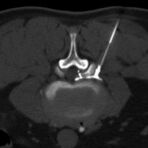

Interventionelle Eingriffe

Durchführung am Standort im Diakonissenkrankenhaus

• z. B. Punktionen zur Gewebsentnahme

Schmerztherapie

(dazu mehr auf der Seite Schmerztherapie)